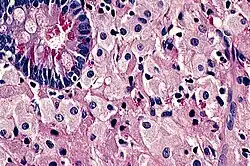

![]() Mikroskopický snímek tenkého střeva u Whippleovy choroby: v lamina propria je přítomný infiltrát zpěněných makrofágů | |